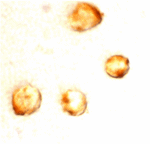

ApplicationsWestern Blot, ELISA, ImmunoCytoChemistry

- ApplicationsWestern Blot, ELISA, ImmunoCytoChemistry